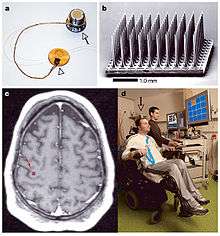

A Brain-computer interface (BCI) is a type of implant that allows for a direct connection between a patient's brain and some form of external hardware. Since the mid-1990s, the amount of research done on BCI's in both animal and human models has grown exponentially. Most brain-computer interfaces are used for some form of neural signal extraction, while some attempt to return sensation through an implanted signal.[3] As an example of signal extraction, a BCI may take a signal from a paraplegic patient's brain and use it to move a robotic prosthetic. Paralyzed patients get a great amount of utility from these devices because they allow for a return of control to the patient. Current research for brain-computer interfaces is focused on determining which regions of the brain can be manipulated by an individual. A majority of research focuses on the sensorimotor region of the brain, using imagined motor actions to drive the devices, while some studies have sought to determine if the cognitive control network would be a suitable location for implantations. This region is a "neuronal network that coordinates mental processes in the service of explicit intentions or tasks," driving the device by intent, rather than imagined motion [9] An example of returning sensation through an implanted signal would be developing a tactile response for a prosthetic limb. Amputees have no touch response in artificial limbs, but through an implant in their somatosensory cortex could potentially give them an artificial sense of touch.

A current example of a brain-computer interface would be the BrainGate, a device developed by Cyberkinetics. This BCI is currently undergoing a second round of clinical trials as of May 2009. An earlier trial featured a patient with a severe spinal cord injury, with no control over any of his limbs. He succeeded in operating a computer mouse with only thoughts. Further developments have been made that allow for more complex interfacing, such as controlling a robotic arm.